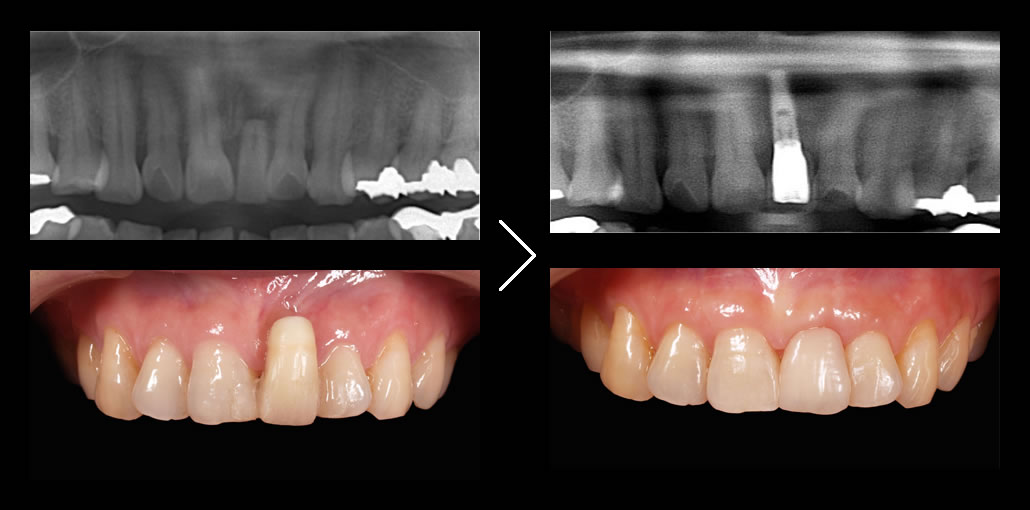

当院が最も得意とするのが前歯のインプラントです。

私たちが最も得意とするのがこの前歯のインプラント治療(審美インプラント)です。誰が見てもインプラントと分からない水準で仕上げることが可能です。

そのため、 骨が残っているところに無計画にインプラントを埋入するケースがほとんどで、その結果インプラントの上部構造の形態に無理が生じたり、見た目の酷い治療結果となりがちです。

他医院では行わない精密な治療計画

オールオン4クリニックでは、必要に応じてインプラント治療前に歯肉や骨の調整を行い、綿密な診査・診断・3Dプランニング・ガイデッドサージェリーを駆使して、寸分のズレのないインプラント埋入を行います。